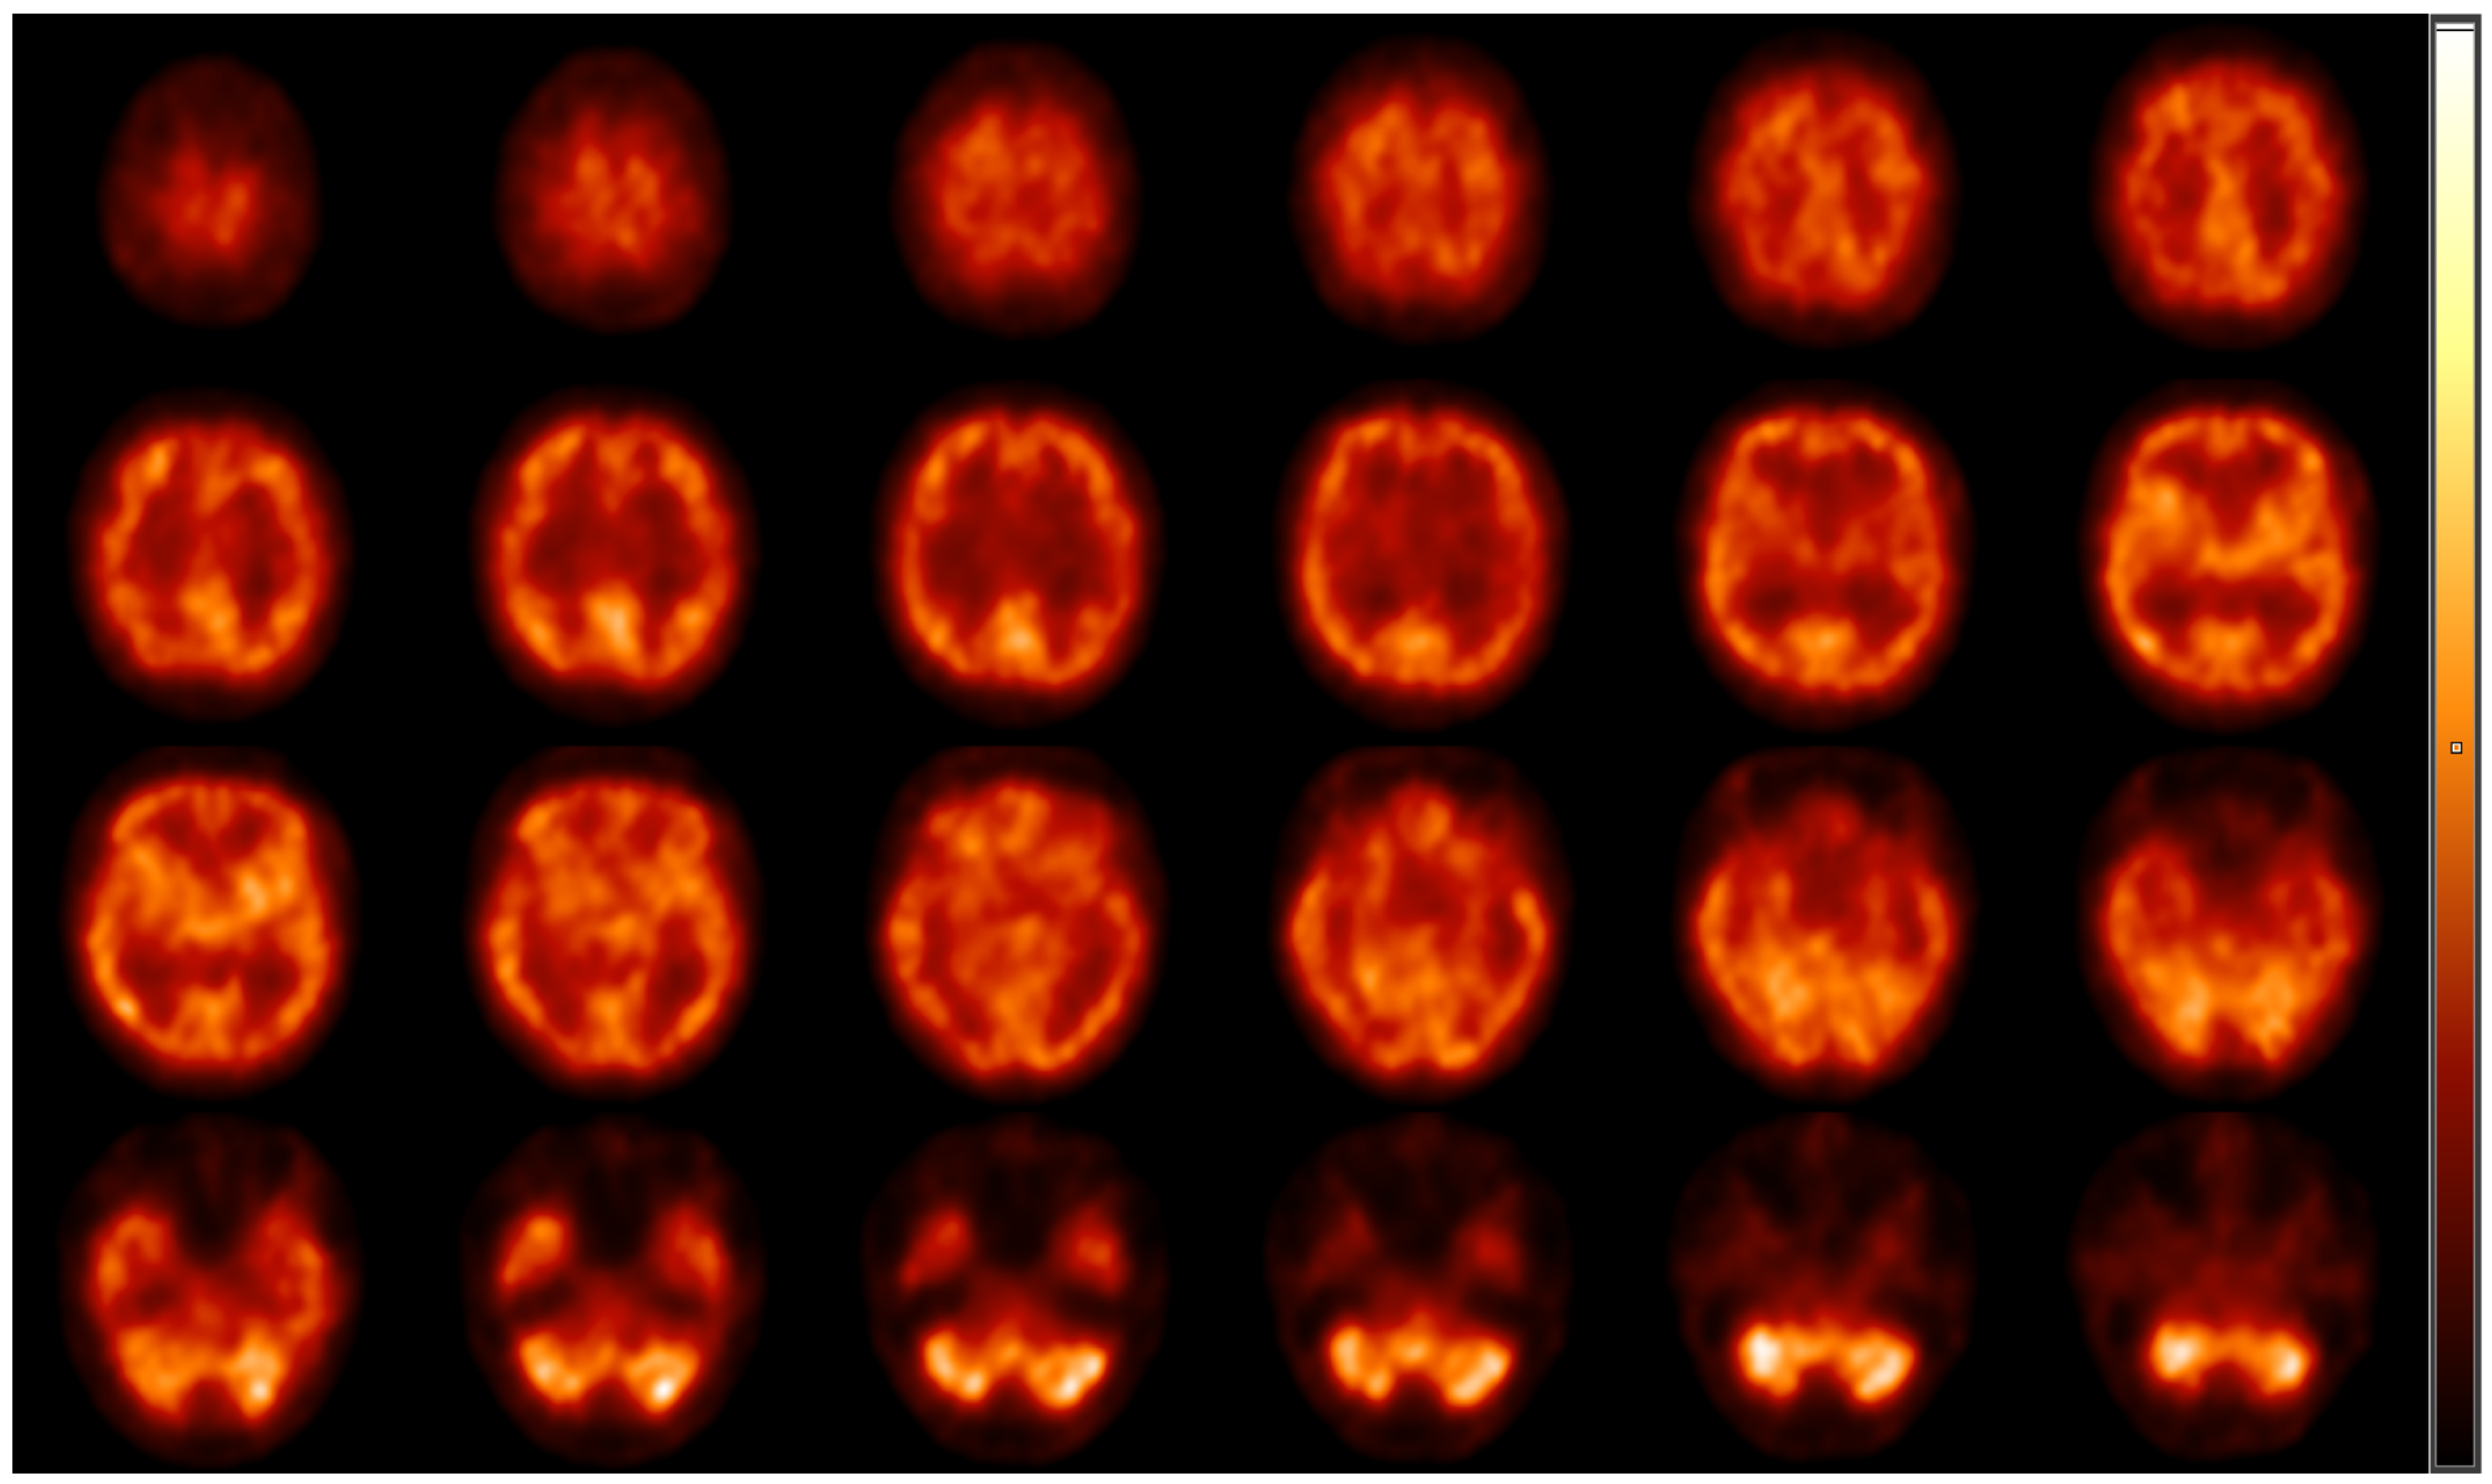

For the evaluation of resting cerebral brain perfusion, we applied a dual-head gamma camera equipped with low-energy, high-resolution parallel hole collimators (AnyScan S Flex, Mediso Ltd., Budapest, Hungary). To prohibit the radiotracer uptake of the thyroid glands, a perchlorate capsule was orally administered to all subjects 30 min prior to radiopharmaceutical injection. After a 10 min rest in a dimly lit room, approximately 740 MBq of [99mTc]Tc-HMPAO was intravenously injected into the right cubital vein of the study participants lying under the camera. Afterwards, SPECT acquisition was conducted with the following imaging parameters: 120 views, 128 × 128 matrix size, 2.36 mm pixel size, 30 s projection time and auto body contour. Representative transaxial brain perfusion SPECT images acquired at rest can be seen in Figure 1. Among the study participants, 6 did not participate in the perfusion SPECT imaging process.

Figure 1. Representative transaxial [99mTc]Tc-HMPAO brain perfusion SPECT images acquired at rest. Following the intravenous administration of 740 MBq of [99mTc]Tc-HMPAO, dynamic SPECT acquisition was performed using AnyScan S Flex SPECT camera (Mediso Ltd., Budapest, Hungary). No perfusion abnormalities can be detected on the slices; the right and the left hemispheres show symmetrical and consistent radiotracer accumulation. High [99mTc]Tc-HMPAO is shown in the cortical grey matter, the region of the basal ganglia and in the visual cortex, while the white matter and the ventricles are presented with faint radioactivity. HMPAO, hexamethylpropylene amine oxime; SPECT, single-photon emission computed tomography.